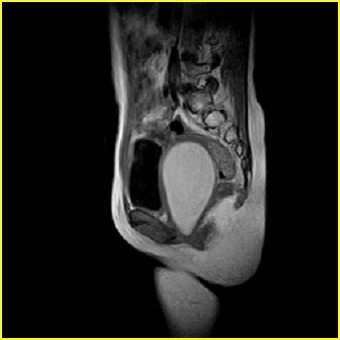

女、15岁、下腹疼痛2天,排尿困难1天。查体:处女膜闭锁,距处女膜约4至5cm处扪及一约5cm直径的圆形包块,张力较高,触痛明显、欠活动。b超提示子宫增大伴宫内增强回声团。

影像意见:子宫直肠陷凹积血。

更正影像意见:阴道积血。

处女膜闭锁,阴道积血

处女膜闭锁,阴道积血,子宫积血.

先天性处女膜闭锁,伴阴道积血,不除外先天性阴道粘液囊肿形成。

阴道积血,子宫积血.

子宫及阴道积血。

处女膜闭锁,伴子宫及阴道积血.